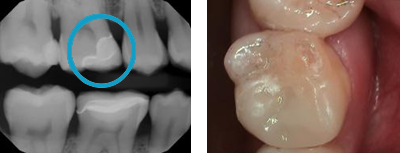

Crown Replacement.

Replaces poor crown margins. Help remove dental decay and restores teeth.

Before: Old bad shaped crown with margin caries

After: New crown with our CEREC technology. Give your tooth a natural look!